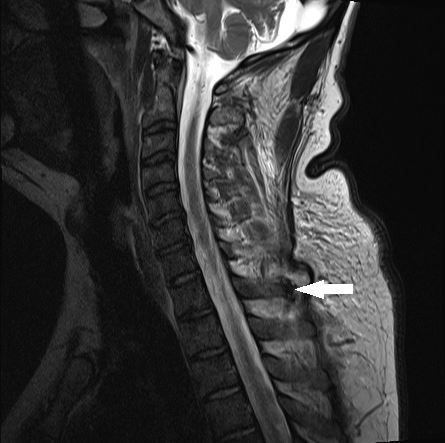

A 41-year-old Australian man with a history of gout presented with severe thoracic back pain and fevers, causing him to be bed-bound for a week. There was no infectious or traumatic precipitating event. This magnetic resonance image of the spine showed a lytic lesion on the T1 spinous process with inflammatory changes in the adjacent soft tissues and surrounded by a small collection of fluid. There was no spinal cord involvement.

The patient was treated for vertebral osteomyelitis and gout until a spinal aspirate showed monosodium urate crystals. He made a full recovery.